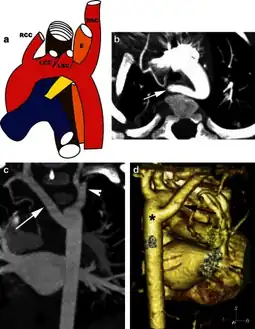

The evaluation of an aberrant subclavian artery can be done via CT angiography[7], which is a combo of CT scan with an injection of dye to produce images of blood vessels and/or tissues [8]

Left aortic arch with an aberrant right subclavian artery -a) Illustration, b)CT scan, c) MIP coronal image, d)coronal reconstructed 3D volume-rendered image